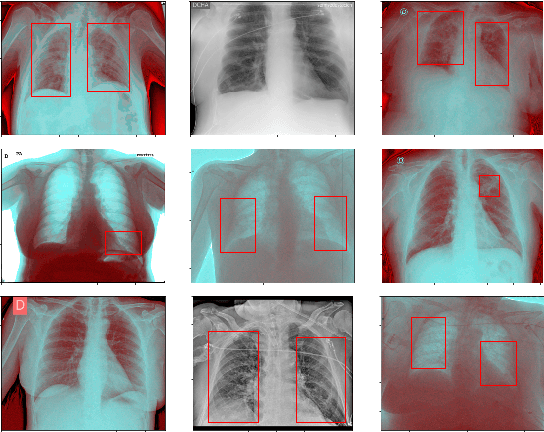

Abstract:This paper proposes transferred initialization with modified fully connected layers for COVID-19 diagnosis. Convolutional neural networks (CNN) achieved a remarkable result in image classification. However, training a high-performing model is a very complicated and time-consuming process because of the complexity of image recognition applications. On the other hand, transfer learning is a relatively new learning method that has been employed in many sectors to achieve good performance with fewer computations. In this research, the PyTorch pre-trained models (VGG19\_bn and WideResNet -101) are applied in the MNIST dataset for the first time as initialization and with modified fully connected layers. The employed PyTorch pre-trained models were previously trained in ImageNet. The proposed model is developed and verified in the Kaggle notebook, and it reached the outstanding accuracy of 99.77% without taking a huge computational time during the training process of the network. We also applied the same methodology to the SIIM-FISABIO-RSNA COVID-19 Detection dataset and achieved 80.01% accuracy. In contrast, the previous methods need a huge compactional time during the training process to reach a high-performing model. Codes are available at the following link: github.com/dipuk0506/SpinalNet